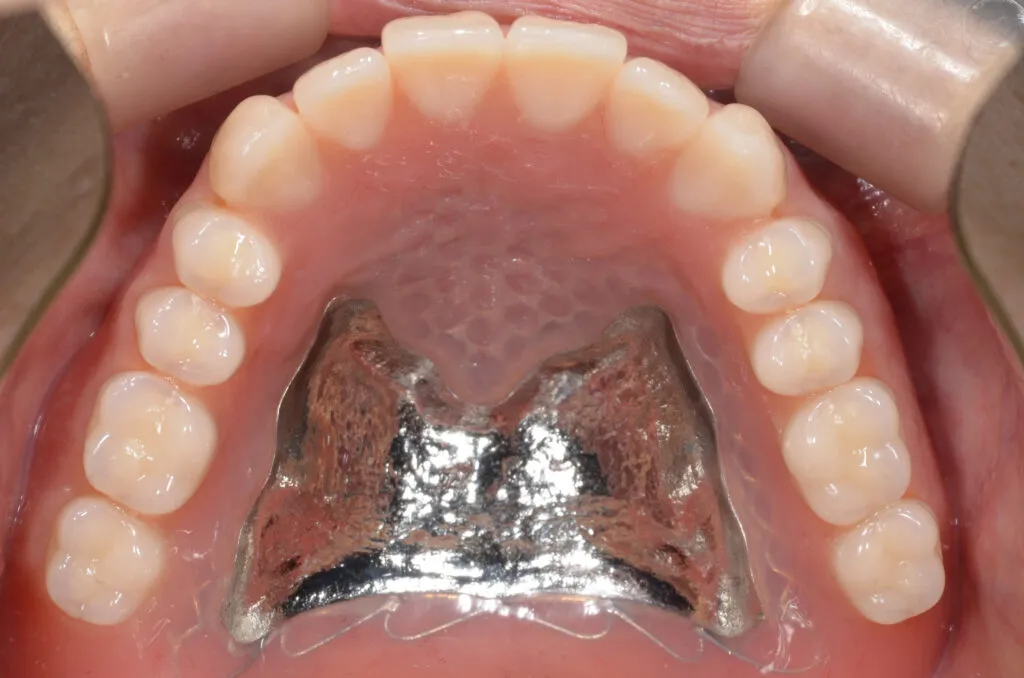

上記写真は当院で上下総義歯を作製した患者さんです

上の写真は当院で上下総義歯を作製された患者さんです

金属床義歯